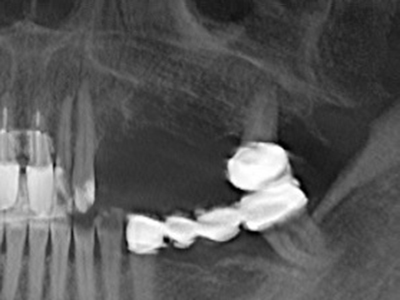

La preparación de la ventana lateral en la elevación del suelo del seno maxilar representa un enorme reto, sobre todo para profesionales de la implantalogía que tienen poca experiencia en técnicas quirúrgicas. Retirar la cobertura ósea del seno maxilar sin provocar daños en la membrana de Schneider es tan solo una parte de la operación; tras crear un acceso suficiente, es preciso movilizar con cuidado la mucosa del seno maxilar a fin de dejar espacio para el material o los implantes que vayan a incorporarse. En esta aplicación la cirugía piezoeléctrica resulta útil en dos sentidos: por un lado, el uso de insertos diamantados permite realizar una retirada selectiva del hueso y, si se actúa con cuidado, la membrana permanece intacta, y por otro lado, las frecuencias de ultrasonidos favorecen también un desprendimiento sin problemas de la membrana, pues se transfieren al espacio comprendido entre la mucosa y el suelo del seno maxilar gracias al uso de piezas romas especiales (Cassetta, Ricci et al. 2012, Pereira, Gealh et al. 2014) (Rickert, Vissink et al. 2013). De este modo, no es de extrañar los trabajos publicados en la actualidad sobre la técnica de elevación del suelo del seno maxilar mediante la técnica de Caldwell-Luc con instrumentos piezoeléctricos (Wallace, Tarnow et al. 2012).

En la cirugía del seno maxilar surgen otros campos de aplicación: En este punto, tras la preparación concéntrica de una tapa ósea de la pared del seno maxilar (que suele tener forma trapezoidal), es posible eliminar patologías y cuerpos extraños del seno maxilar. La tapa ósea se repone después de finalizar la parte intra-antral de la operación y se asegura frente a una posible dislocación mediante cuñas o suturas adaptables.